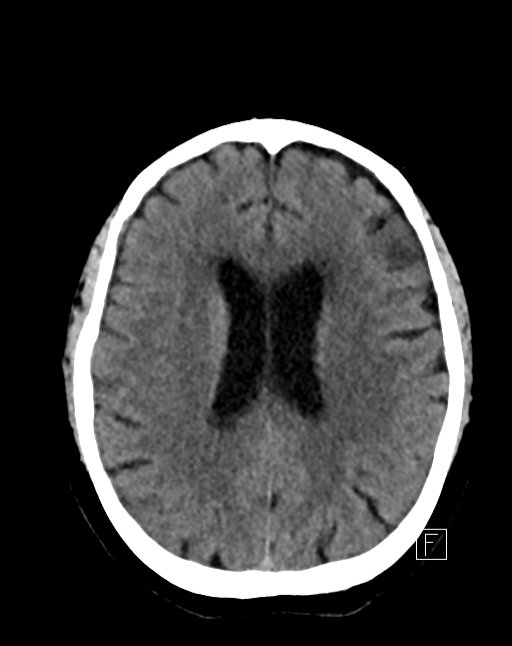

Post treatment CT head: normal